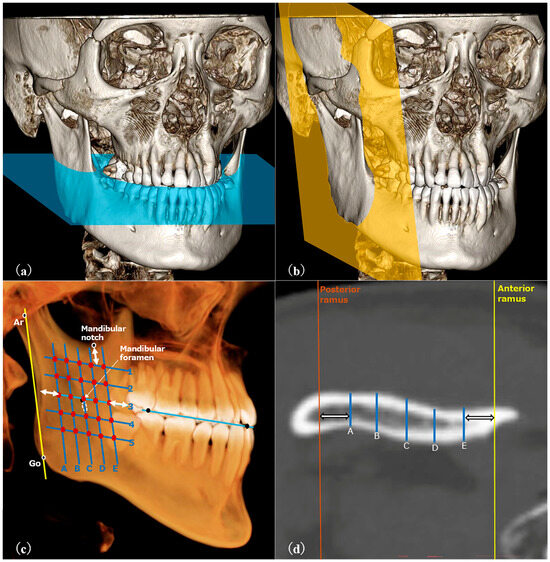

Figure 2.

(a–d) CT images viewed with DICOM viewer. (a) The axial plane (blue plane) was parallel to the occlusal plane. (b) The para-sagittal plane (yellow plane) was parallel to the ramus. (c) Five oblique lines, parallel to the ramus’s posterior border and 5 mm from its surfaces, were drawn. Five evenly spaced horizontal lines intersected the middle oblique line 5 mm below the ramus’s top. Thickness was measured at 25 points to average the ramus’s thickness. (d) An example of measurement at a certain cross-section.